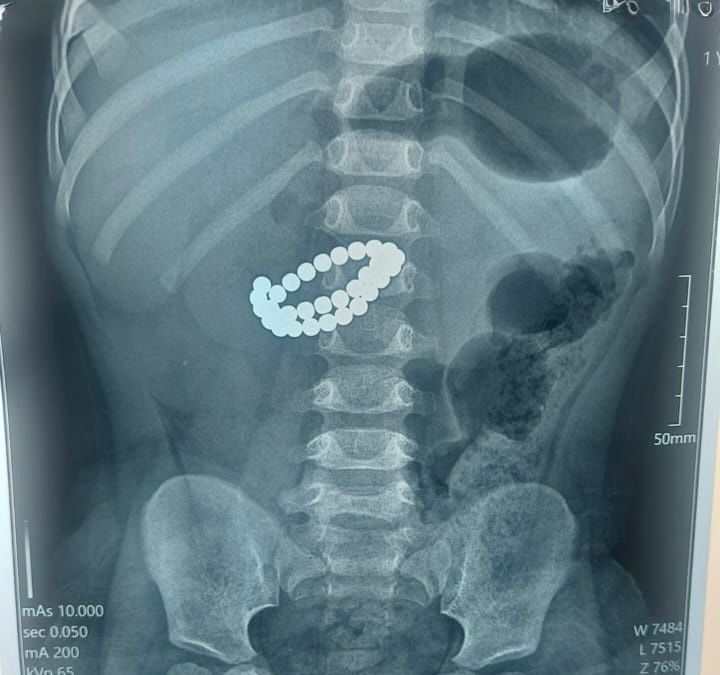

Бала өте ауыр жағдайда қабылдау бөліміне жеткізілген. Тексеру нәтижесінде дәрігерлер «ішектегі бөгде заттар — 31 магнит, жіңішке ішектің бірнеше тесілуі, перитонит» деген диагноз қойған.

Баланың өмірін сақтаудың жалғыз жолы – шұғыл хирургиялық ота болды. Дәрігерлер ортаңғы лапаротомия жасап, құрсақ қуысы ағзаларын толық тексерді. Ота барысында магниттер ішектен алынып, жіңішке ішектегі барлық тесіктер тігіліп, құрсақ қуысы тазартылды және дренаж орнатылды. Сонымен қатар ішекке трансаналдық интубация жасалды.